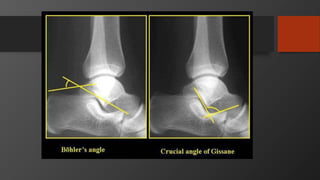

Imaging

• AP, Lateral

• Harris view

• CT scan

• Gold standard